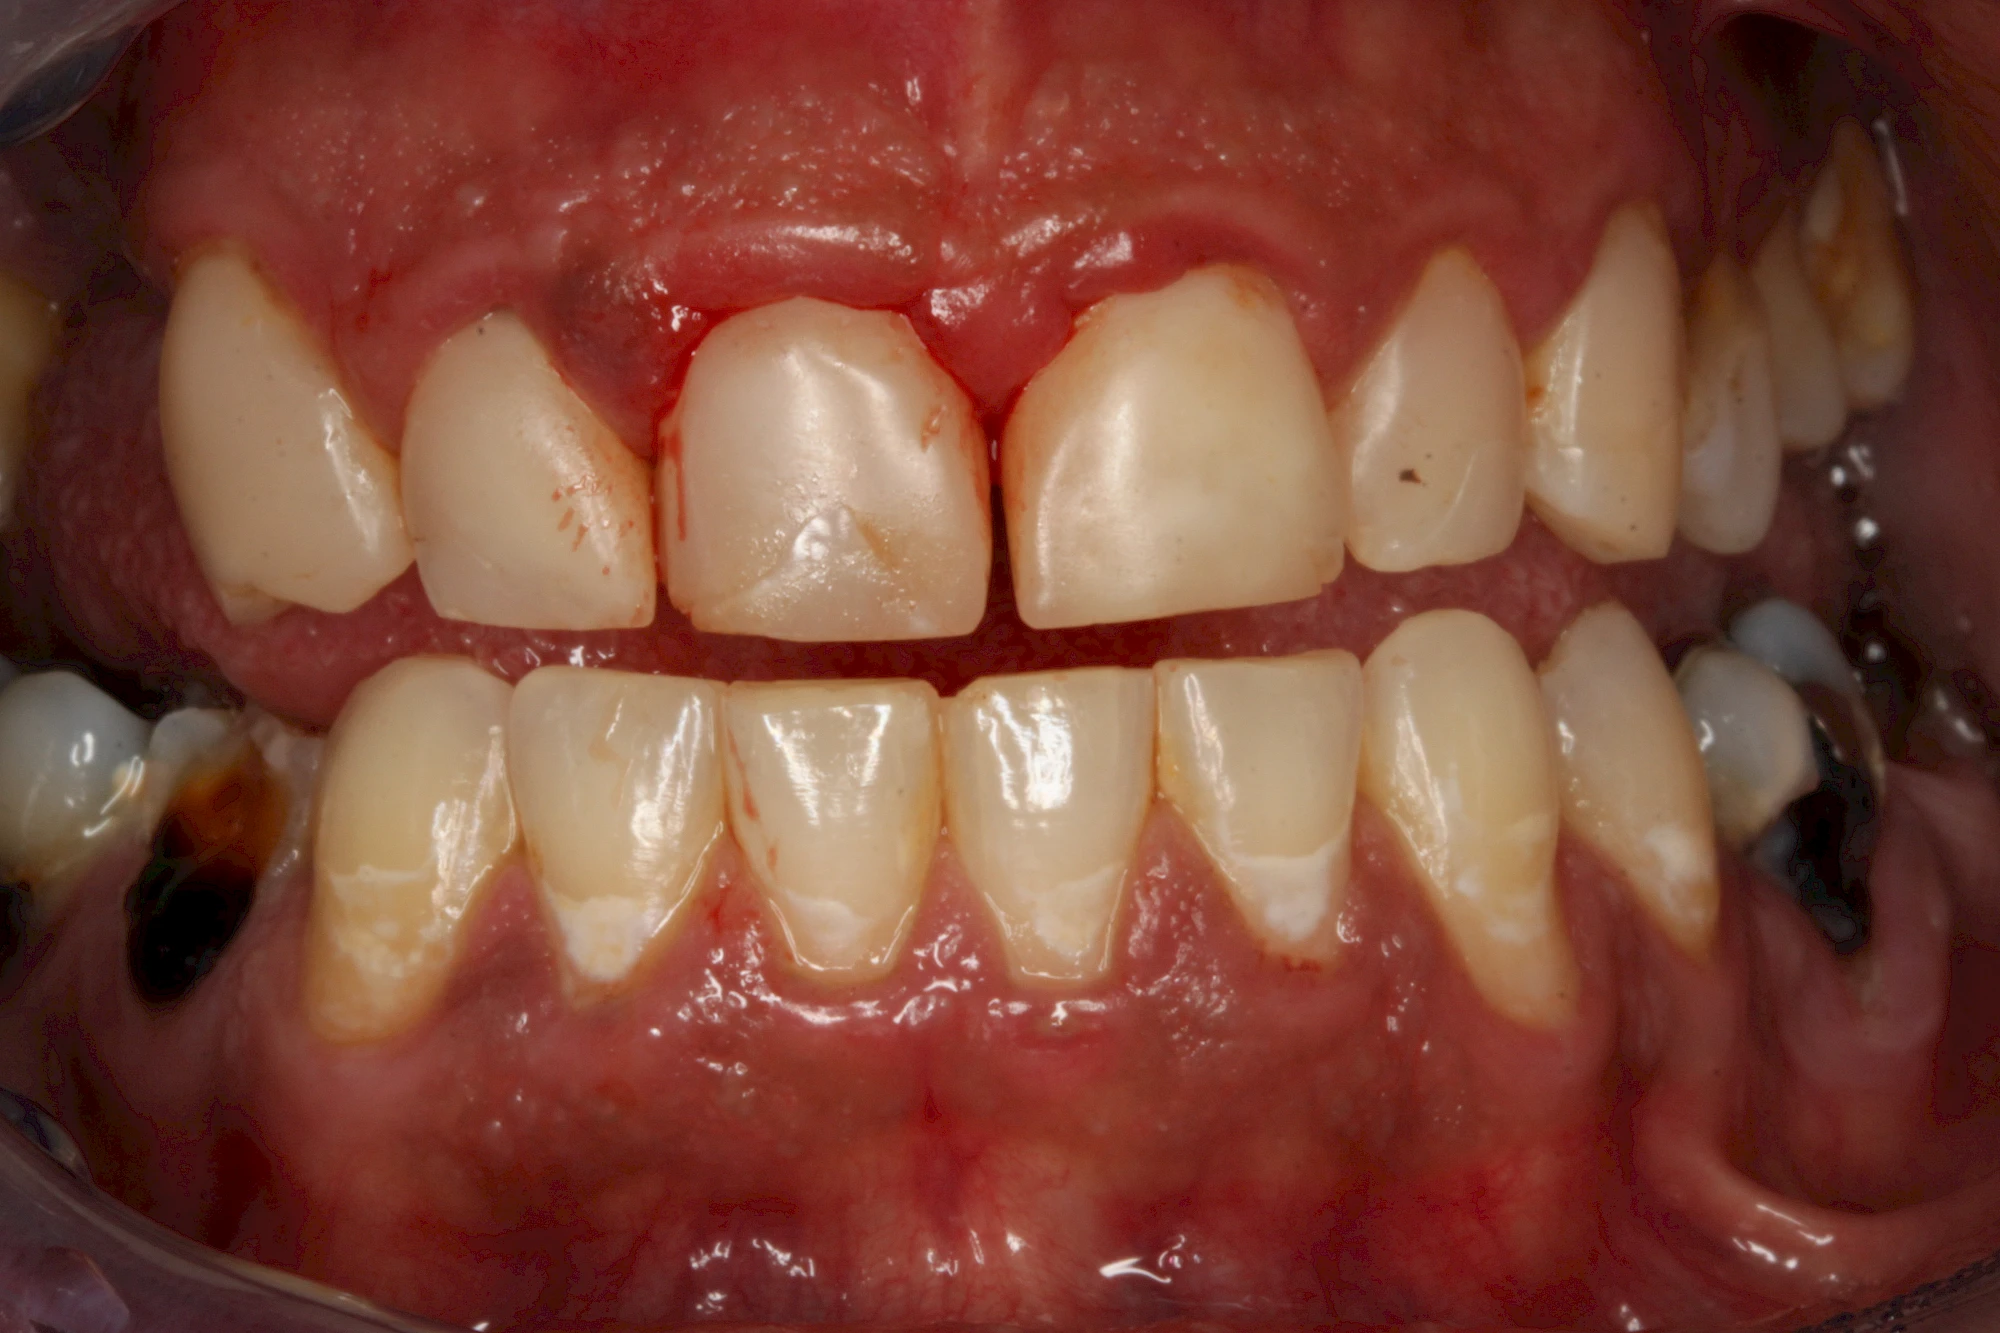

Gerade bei Kindern und Jugendlichen werden zunehmend häufiger bräunliche Verfärbungen mitunter auch mit Formveränderungen (die Oberfläche ist rauh oder zerklüftet) der Zähne beobachtet. Meist sind Schneidezähne oder Backenzähne betroffen. Dies könnte ein Hinweis auf sogenannte Kreidezähne (MIH: Molaren-Inzisiven-Hypomineralisation) sein.

Bräunliche Verfärbung